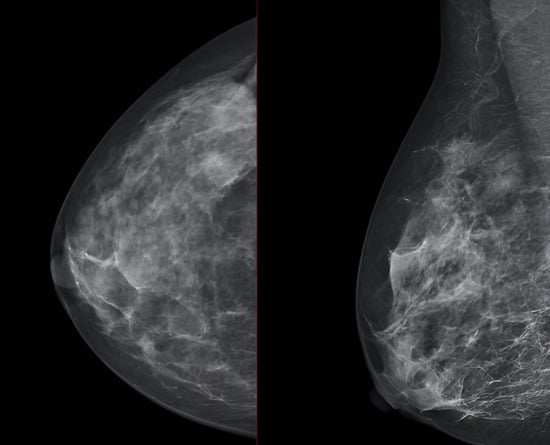

We report the case of a 47-year-old pre-menopausal Caucasian woman who presented to the Policlinico Umberto I hospital in Rome, with a 6-month history of subjective dizziness, oscillopsia, instability, imbalance, blurred vision, and photophobia, accompanied by severe vomiting, which resulted in severe weight loss (16 kg over 7 months) (Table 1). The medical history was significant for only hypothyroidism and her family history was positive for a sister with breast cancer. Clinical examination of our patient revealed marked fluctuations without prevalence to the side during Romberg and Fukuda tests, both with open and closed eyes. In video-oculoscopy (Supplementary Materials Video S1), the assessment of extraocular motility demonstrated isolated and intermittent episodes of low-amplitude, high-frequency horizontal saccades occurring without an intersaccadic interval, consistent with the clinical presentation of ocular flutter []. A comprehensive evaluation was performed, including contrast-enhanced brain Magnetic Resonance Imaging (MRI) (Figure 1), brain Computed Tomography (CT) scan (Figure 2), ophthalmological assessment, viral serology, autoimmune panel, complete blood count, and assessments of thyroid, renal, coagulation, hepatic function, vitamin D and B12 levels; all results were within normal limits. Paraneoplastic syndrome (ENS) sometimes precedes the diagnosis of cancer, necessitating a screening to detect an unidentified tumor. After excluding all other potential causes of the neurological symptomatology, a paraneoplastic origin was considered. Paraneoplastic autoantibody panels (anti-Ri, anti-Yo, anti-Hu, anti-CV2.1, anti-Amphiphysin, and anti-Ma2/Ta) resulted positive for anti-Ri onconeural antibodies with a value of 1:126 (51–256 strong positivity). A whole-body CT scan revealed multiple solid non-calcific nodules (at least 4 in the right breast QQEE), the largest measuring 13 × 9 mm, and right axillary lymphadenopathy measuring 24 mm (Figure 3). Mammography showed at least three nodular opacities with an irregular shape in the external superior quadrant of the right breast. The biggest ones were 13 mm (with intranodular microcalcifications) and 12 mm (BIRADS 5) (Figure 4). The breast ultrasound confirmed three solid irregular hypoechoic nodules measuring 11 mm, 9 mm, and 12 mm, as well as some right axillary lymphadenopathy, the largest measured 25 mm (Figure 5). Histological examination of an ultrasound-guided biopsy revealed invasive carcinoma “no special type” (NST) according to the 2019 World Health Organization (WHO) classification, with a grade 2 histology (G2) with occasional outbreaks of ductal carcinoma and axillary lymph node metastasis. Additionally, a bone scan revealed no evidence of the disease’s metastatic localization (Figure 6). A multidisciplinary team decided to proceed with a right mastectomy and a right axillary dissection. The final histopathological report showed an invasive multifocal NST grade 2 carcinoma, positive for ER (98%), PR (80%), Ki67 (32%) and negative for HER2 (Luminal B HER2 negative). The resection margins were free of neoplastic infiltration. Two of the 14 lymph nodes were positive for invasive carcinoma. The final staging was G2 pTle pNla (2/14) MO, stage IIA. The patient received hormone therapy (Exemestane 25 mg daily and Decapeptyl 3.75 mg daily) due to high hormone receptor expression. Surgical treatment of the primary tumor did not improve neurological symptoms, prompting the patient to undergo intravenous steroid therapy; however, this also did not lead to any clinical improvement. The patient was evaluated at 2, 6, 12 and 24 months with clinical, radiological and serological examinations. On vestibular examination 2 months post-surgery, subjective dizziness and instability persisted. On video-oculoscopy, the patient presented ocular flutter with intermittent horizontal saccades especially in the lateral gaze. Total body CT scan (Figure 7) and breast ultrasound (Figure 8) at 2 months were negative for neoplastic recurrence or metastases. Serology for anti-Ri antibodies remained positive. Six months after surgery, the patient, who had been on Prednisone 50 mg/day, was admitted to the neurology department of another hospital. Patient reported an improvement in headache and a reduction in the frequency of emesis, but no improvement of the ocular and vestibular symptoms. The neurological examination documented oculovestibular syndrome with ocular flutter that was not inhibited by fixation, forcing the patient to keep her eyes closed, ataxia, head and trunk tremor, hypomimic facies, hypertonia in the right upper limb with difficulty in movements of the right hand, difficulty getting up from the chair without support, instability in open and closed eyed Romberg test, moon facies due to iatrogenic Cushing’s, slow, diprosodic and hypophonic speech. During admission, an MRI of the brain and brainstem was performed, which showed a slight enlargement of the peri-brain spaces in the frontal area and of the peri-brain spaces in the cerebellar area, possibly indicative of initial atrophy. Blood tests confirmed the presence of anti-Ri antibodies. Considering the immune-mediated genesis of the paraneoplastic syndrome, the patient underwent five sessions of plasmapheresis followed by a course of intravenous immunoglobulin (0.4 g/kg/day) with a slight and temporary clinical improvement. Due to the presence of a mild right rigid-kinetic hemi-syndromes with associated hypomimia and hypophonia, a genetic study for Parkinson’s disease was conducted and L-DOPA therapy was prescribed, which was then discontinued as the patient reported worsening symptoms. The patient underwent brain SPECT with receptor tracer to evaluate the presynaptic dopaminergic system the basal ganglia, which showed no impairment of the nigrostriatal presynaptic dopaminergic system. Due to the lack of response to chronic steroid therapy and the development of clinical signs of iatrogenic Cushing’s, following endocrinological consultation, the dosage of Prednisone was progressively reduced and then replaced by Cortone Acetate. Bone mineral density was normal. After one month, the patient was transferred to a rehabilitation center to undergo neuromotor and vestibular rehabilitation until the patient was transferred back to the prior neurology department due to a clinical worsening, in particular of the eye complaints. The patient was unable to perform more than a few steps without support, showed multidirectional fluctuations on the Romberg test with trunk instability. At eye opening there was persistence of the ocular flutter, with mydriatic pupils (left > right) and a cloudy but present response to direct light stimulus. The other cranial nerves were intact. Thermal tactile and pain sensitivity were preserved. Osteotendinous reflexes were brisk and symmetrical in the upper limbs and hypotensive in the lower limbs. Coordination tests (index-nose, index-index, finger-tapping), revealed mild motor impairment on the right side with kinetic and postural tremor and fine tremors in the upper limbs. During hospitalization, the patient underwent a new course of plasmapheresis (four sessions in 8 days) combined with intravenous immunoglobulins (0.4 g/kg/day for 4 days) with slight clinical benefit. Due to the need for chronic immunosuppressive treatment, oral therapy with Azathioprine at an initial dosage of 25 mg/day, later increased to 50 mg, was administered. A contrast-enhanced MRI of the brain and cervical spine was performed, which showed essentially unchanged findings compared to the previous check-up, including a modest enlargement of the peri-brain spaces in the frontal area and peri-foliar spaces in the cerebellum, expressing initial signs of atrophy. Slight clinical improvement was documented during hospitalization, particularly in head tremor and ocular flutter, allowing the patient to fixate, despite the persistence of pathological eye movements. Gait was improved, although the patient remained ataxic. In view of this progress, the patient was again transferred to the neuromotor rehabilitation center for one month at the 12 months follow-up visit, the patient reported a worsening of the oculovestibular syndrome with inexhaustible flutter preventing fixation, worsening of rigidity in the right upper limb and occasional dysphagia. The neurological examination showed dystonic flexion in the right upper limb and plastic hypertonia in the upper limbs bilaterally (right > left), but no hypertonia in the lower limbs. Independent ambulation was not possible. The patient had an intravenous infusion of cyclophosphamide, which brought only slight and transient improvements in symptoms. After 24 months from the surgery, the patient was re-evaluated in our hospital, and a vestibular examination via oculoscopy confirmed the presence of the flutter with horizontal saccades, which were slightly reduced compared to the first assessment in 2022. Vestibulospinal tests revealed a severe postural deficit, with ataxic walking and right upper limb rigidity.

Figure 5. Ultrasonographic image showing irregular, solid, hypoechoic nodules (red lines), suspicious for malignancy. Axillary lymph nodes are also visible (indicated by orange arrows and lines), some of which display altered morphological features.